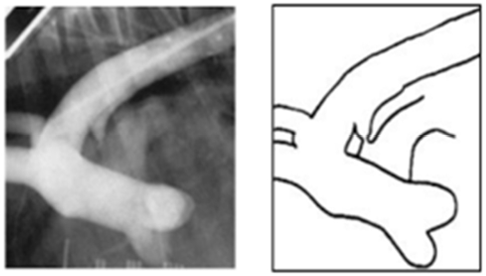

| 1기 (Moderate : 좌심방귀 볼록한 정도) |

![]() |

| 1) 심장 커짐 Cardiomegaly, left auricle 확장, 전허리/후허리 소실 : 심장이 부풀면서 일자형이 됨. + Sternal contact : 심장과 sternum 거리 좁아짐 2) 기관에 영향 좌심방 비대 ⇒ 기관 상승, carina를 눌러서 기침 유발 (주로 밤에 기침) : tracheal elevation, bronchial collapse, noctural cough |